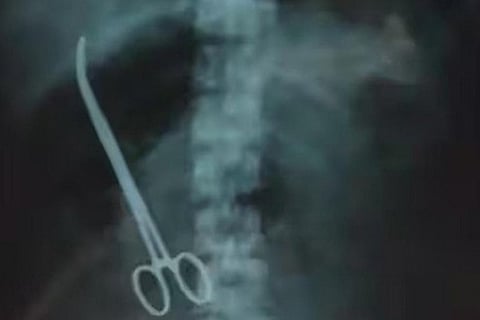

Various tests, including x-ray were conducted, at the Vijayawada Hospital and to their utter shock, the x-ray showed forceps in her stomach. However, the issue came to light when a hospital employee posted a photo of the x-ray on his social media accounts.

Artery forceps are used to control bleeding from blood vessels by clamping the artery. However, the doctor who performed the procedure forgot to remove the same.